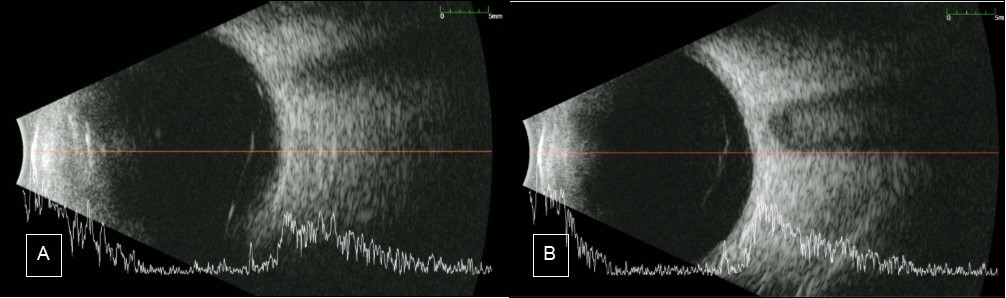

Figure 5.B-scan A) Case 1 Right eye: shows an almost complete PVD with remaining attachment to the optic nerve. B) Case 2 Right eye shows complete PVD

B-scan A) Case 1 Right eye: shows an almost complete PVD with remaining attachment to the optic nerve. B) Case 2 Right eye shows complete PVD

Going back to our patients, around 50% of the retina is still visible and the hemorrhage was confined at the posterior vitreous cavity near the retina. Ocular ultrasound (B-scan) was done to the 2 patients’ affected eye and both showed liquified vitreous. For the first case, posterior vitreous detachment (PVD) was almost complete, the only remaining attachment is to the optic disc. On the other hand, there was a complete PVD for the second case. (see Figure 5). The status of PVD in our patient means that there is less scaffold for neovascular tufts and preretinal membranes to develop. Both patients also underwent PRP. ‘The main goal of PRP is the destruction of retinal cells in the areas of hypoxia, especially muller cells which are responsible for upregulation of VEGF. Another therapeutic effect of PRP is the induction of PVD. Studies have shown (Sebag, 1990 cited by Kroll7) higher incidence of PVD following PRP. Progression of PVD can be observed 3-6 months following PRP’7 Thus, PRP might have promoted PVD in our patients.